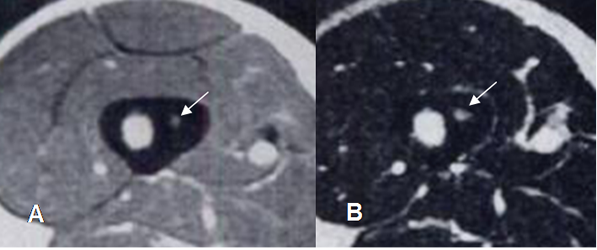

Fig 62. Osteoma osteoide.

A: RM coronal en T1 y B: RM coronal en STIR. Osteoma osteoide hipointenso en T1 e hiperintenso en STIR, con nido central hipointenso.

Fig 63. Osteoma osteoide.

A: RM axial en T1 con contraste y B: RM axial en T2. Nido no calcificado, hiperintenso en T2 y que realza con el contraste.